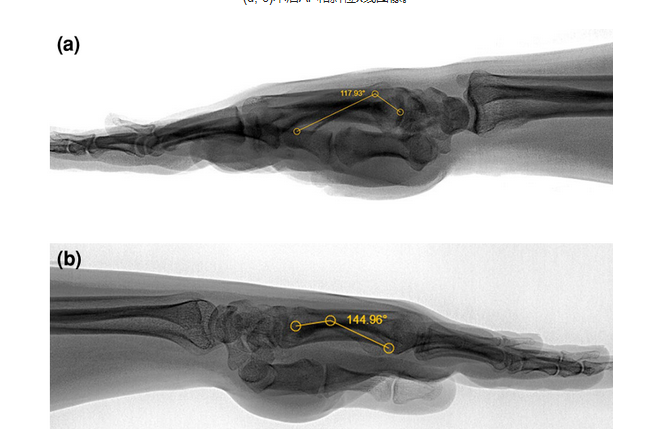

保守治疗2例屈曲畸形角度测量。(a)屈曲角度62°(118°)。(b)屈曲角度35°(145°)